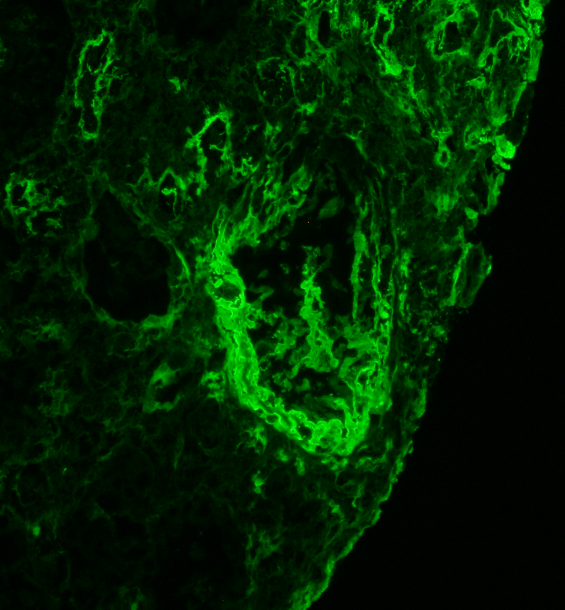

Severe vascular rejection hiding in the IF tissue. Fibrinoid necrosis really pops on the H&E and further confirmed by fibrinogen IF. #renalpath #pathtwitter #nephrology